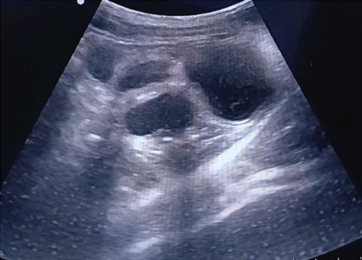

Diagnosis is made by a combination of history, clinical signs, and abdominal imaging. Bloodwork can be beneficial in supporting a diagnosis of pyometra and, more importantly, assessing the patient’s systemic health. Overall, Ultrasonography is the most helpful diagnostic tool for identifying pyometra. Often, distended fluid-filled loops of the uterus are visible on ultrasound adjacent to the urinary bladder. However, the differential diagnosis of mucometra and hydrometra has been noted to appear similarly on ultrasound. Strictly speaking, a definitive diagnosis of pyometra is made and verified through postoperative macroscopic and histologic examination of the uterus and ovaries, as well as microbiological examination of the uterine content.

Ultrasound Imaging of a confirmed case of canine pyometa. The Patient’s Urinary Bladder (UB) is visible adjacent to distended loops of uterine horn in transverse section, indicated by an asterisk (*). Reddy et. al. J. Andaman Sci. Assoc. 29 (2 ):2024